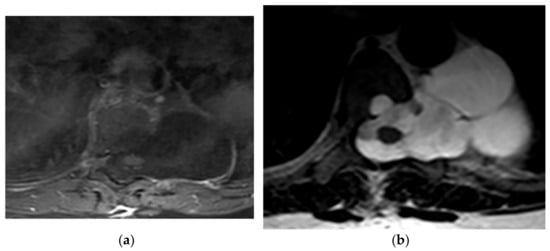

Figure 4.

A 28-year-old man with bilateral leg weakness. The axial non-contrast-enhanced CT in the bone window (a) demonstrates a destructive mass in the posteromedial aspect of the chest wall on the left side, with a prominent soft tissue component with the left lateral vertebral body, pedicle, and lamina destruction (arrow). Axial T1W (b) MRI shows an inhomogeneous mass with iso to hyperintense signal intensity to paraspinal muscle with extension and invasion to left lateral recess, adjacent chest wall muscles, and rib (arrow).